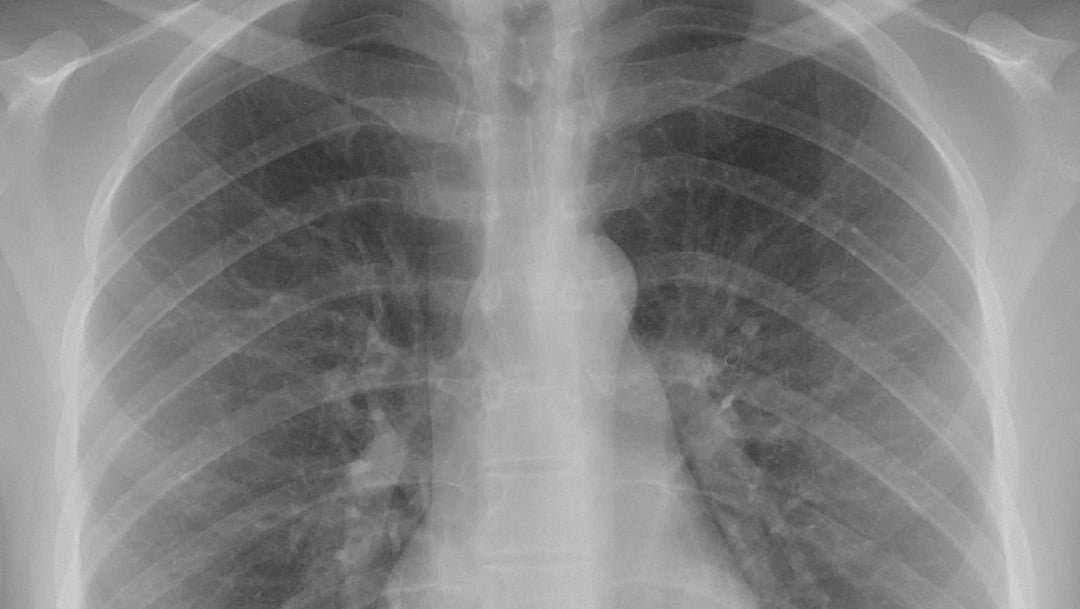

🔊 Escuchar esto La pandemia del Covid-19 sigue abriendo muchas interrogantes. Si bien la mayoría de los pacientes solo experimentan síntomas leves a moderados, hay un grupo de sobrevivientes que nunca se han recuperado. De acuerdo con un nuevo estudio, estos pacientes presentan daño crónico en los pulmones y fatiga crónica. Un equipo de científicos de la Universidad del Sur de California en Los Ángeles (UCLA) comenzó a rastrear a los pacientes con Covid-19, utilizando una tomografía computarizada para examinar sus pulmones. Siguieron a 33 pacientes durante un mes. CICATRICES EN PULMONES Los resultados de su trabajo, que fueron dados a conocer en la revista Nature, muestran que más de un tercio de los pacientes tenían muerte tisular que aparecía como cicatrices en sus pulmones. Los investigadores planean seguir a estos pacientes durante años para determinar los efectos duraderos del Covid-19 en el cuerpo. Según Ali Gholamrezanezhad, radiólogo clínico y parte del equipo, la mayoría de los casos son de leves a moderados y no terminan ingresando en el hospital. Estima que la tasa de daño pulmonar a medio plazo es de menos del 10 por ciento. Sin embargo, dado que hay alrededor de 34 millones de personas en todo el mundo que se infectaron (de acuerdo con el mapa de la Universidad Johns Hopkins), incluso un porcentaje bajo puede implicar que miles de personas experimentan problemas de salud persistentes y duraderos. PREOCUPACIÓN POR ALZA DE CASOS Dado que muchas personas tienen síntomas persistentes, a muchos médicos les preocupa que el número aumente a medida que aumentan los casos. La enfermedad es nueva y nadie tiene idea de sus efectos a largo plazo en el cuerpo. A los médicos les preocupa que el daño a los órganos sea permanente o persista durante meses o incluso años. Tampoco están seguros de si el daño probablemente se deba a tratamientos intensivos, como la intubación, o si es causado por el virus mismo. Sin embargo, a medida que evoluciona la pandemia, muchos estudios nuevos muestran que el virus ataca a muchos órganos, no solo a los pulmones. (Foto: Tomada de Noticieros Televisa) Compartir